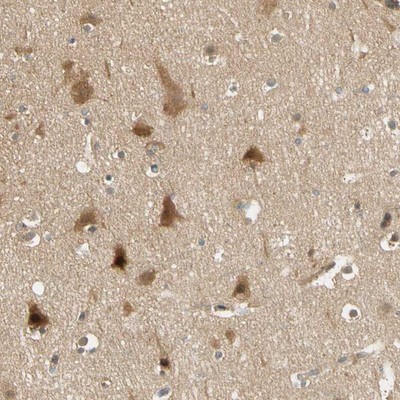

Supportive validation

- Submitted by

- Novus Biologicals (provider)

- Main image

- Experimental details

- Immunohistochemistry-Paraffin: PDDC1 Antibody [NBP1-93843] - Staining of human cerebral cortex shows distinct cytoplasmic positivity in neurons.